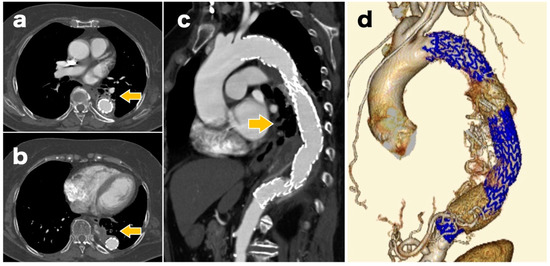

A 77-year-old woman underwent graft replacement of the descending aorta for a descending aortic aneurysm 18 years prior. Postoperatively, aortic dissection was observed at the proximal and distal anastomoses of the graft, and the patient was regularly followed up with computed tomography (CT) in the outpatient department. At 3 months prior to admission, the patient developed a cough with bloody sputum, and due to the persistent symptoms, she was admitted for a thorough examination. On admission, a contrast-enhanced CT scan showed infiltrative shadows and gaseous images in the lung fields around the graft (Figure 1). Gallium scintigraphy also showed abnormal accumulation of gallium consistent with the infiltration shadows and gas images of the lung fields observed on contrast-enhanced CT (Figure 2). Based on these imaging findings, ABF was diagnosed. The patient was considered to be at high risk owing to her advanced age and post-graft replacement of the descending aorta; therefore, TEVAR was performed on the 11th day after admission.

Figure 1. Contrast-enhanced computed tomography scan on admission showing infiltrative shadows and gaseous images in the lung fields around the graft (arrow). Although we could not directly signify the fistula between the aorta and the bronchus, the clinical history and CT findings led to the diagnosis of aortobronchial fistula ((a,b): axial images; (c): sagittal image). Chronic aortic dissection findings are also observed on the proximal side of the graft replacement (arrowhead). CT, computed tomography.

The causes of ABF include thoracic aortic aneurysm, advanced lung cancer, lung infection, and graft replacement or TEVAR for thoracic aortic aneurysms. Among these, previous thoracic aortic surgery is the most common cause, with 55% of all cases including a previous thoracic aortic surgery [3]. It has also been reported that the most frequent site of ABF is between the descending aorta, left lung, and/or bronchus [1,2]. Hemoptysis is a typical symptom, and shock may occur if the amount of bleeding is large [6]. A CT scan may aid in the prompt diagnosis of ABF with infiltrative shadows and hematoma images observed in the lung fields around the aorta. However, fistulas between the aorta and bronchus are rarely directly detectable on CT images [4]. In this case, the patient had hemoptysis, a cough that persisted for 3 months, and underwent descending aorta replacement surgery 18 years ago. In addition, CT images showed infiltrative shadows and gaseous images in the lung fields around the graft, suggesting a fistula between the graft and the left lung and/or bronchus, leading to ABF diagnosis.